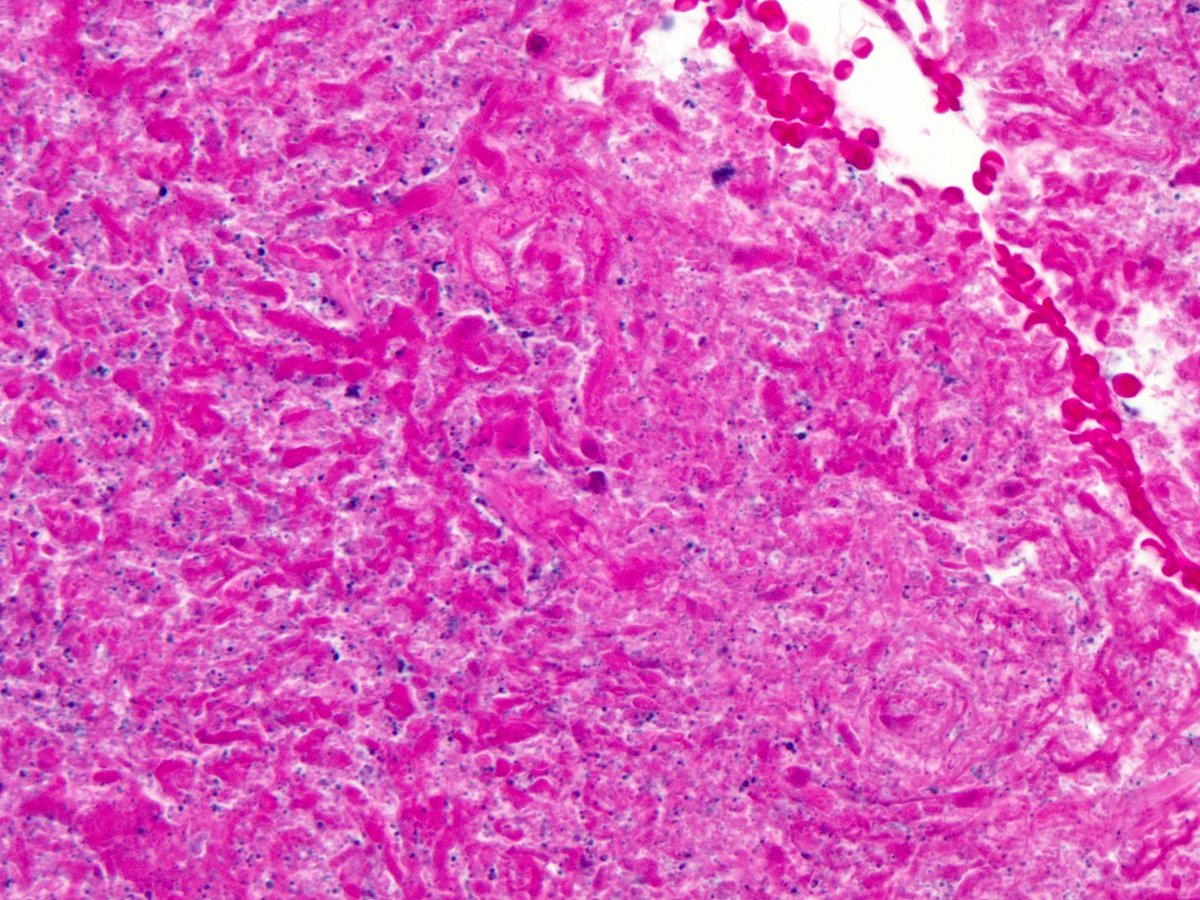

Priti Agarwal, MD, MHS Celina Stayerman MD 16. Most fungi are visible on routine stains like H&E or pap. As a PGY1, ask yourself: "are these fungi yeasts or hyphae". Yeasts (left) are round (ish), hyphae (right) are elongated. Warning: hyphae cut in cross section can mimic yeasts (green circles) #pathbugs

Priti Agarwal, MD, MHS Celina Stayerman MD Ayat Ghazy Vaishali Masatkar, MD baatseba @GermHunterMD 17. Lung neuroendocrine tumor tip for PGY1s: carcinoid tumors can have elongated nuclei and look like a spindle cell tumor (This stain is a Diff Quik, used in cytology)